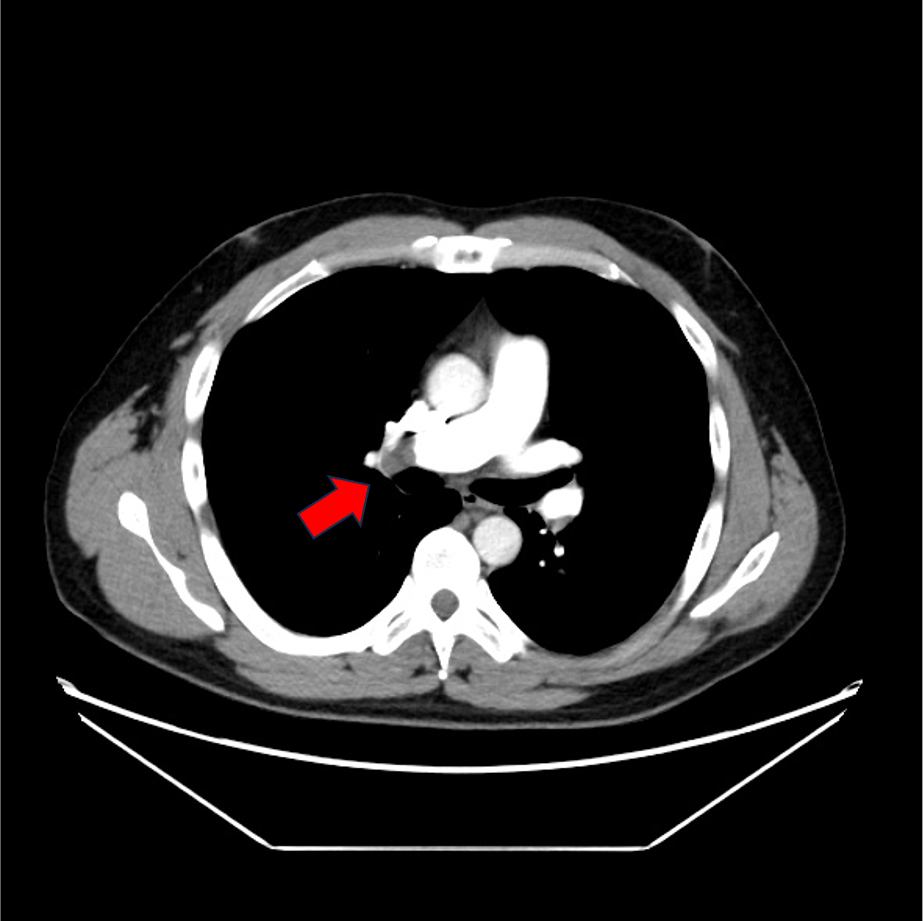

症例は40歳代男性。左下腿の浮腫、疼痛と労作時息切れを認め、血液検査にて血清D-dimerが高値であったため、肺血栓塞栓症の精査目的に造影CTが施行された。両側肺動脈と両側下肢静脈に造影欠損域を認め、それぞれ肺血栓塞栓症、深部静脈血栓症が考えられた。その後、抗凝固療法が施行されて血栓は縮小し、退院となった。

当該疾患の診断における造影CTの役割

肺血栓塞栓症(PE)の診断にはCTが第一選択となる。肺血栓塞栓症の原因の多くは深部静脈血栓症(DVT)であるため、PEが疑われる場合には速やかにDVTの検索も同時に行われることが望ましい。DVTの検査法としては、超音波検査も挙げられるが、胸部の肺動脈相を撮像の後に骨盤部~下肢の静脈相を撮像することで一度に塞栓源の検索が可能となる。これにより速やかな診断と方針決定に寄与することができる。CTではPE、DVTともに血管内の造影欠損を確認することにより診断となる。その他、右心系の負荷評価や他疾患の鑑別も容易になること、低侵襲的に検査できるといった点がCTの利点として挙げられる。一方で、末梢の微小血栓が描出困難な場合や呼吸変動によるアーチファクトで画質低下が生じることがある。また被曝量が比較的多く、臨床情報から適応を判断することが重要である。

CT技術や撮像プロトコル設定について